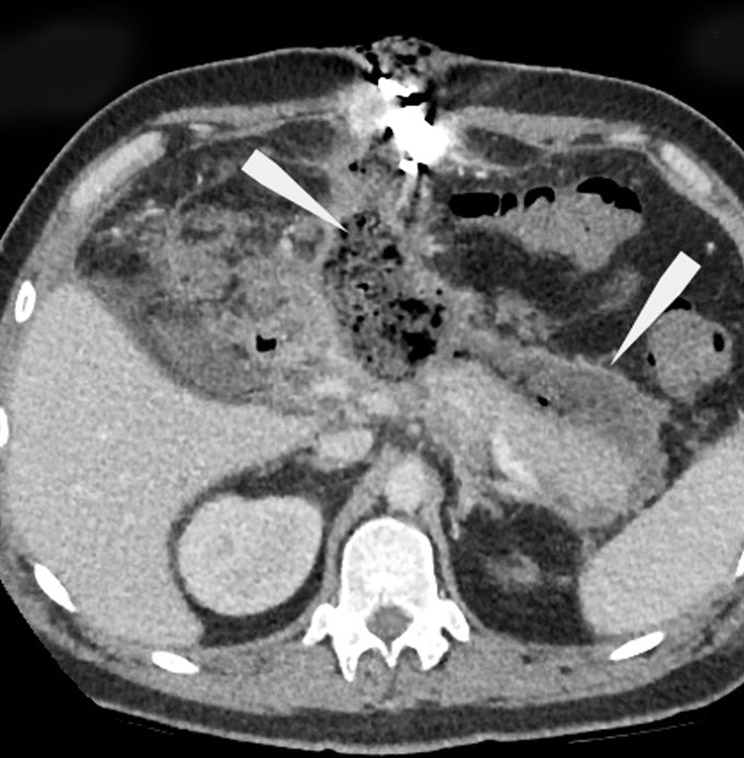

The increasing role of functional visualization modalities for navigation of external beam radiation therapy and brachytherapy in prostate cancer

Brachytherapy is successfully used in the treatment of malignant neoplasms in males and females and rare cases in children, as an independent method (with localized prostate cancer) or adjuvant with remote focal radiation therapy (with cancer of the cervix, anal canal, head and neck, breast, etc.).

The expansion of diagnostic capabilities (the advent of computer and magnetic resonance imaging) due to three-dimensional imaging has given brachytherapy an important technological advantage over other methods. Many options are available for combining brachytherapy with remote radiation or systemic antitumor therapy in the first line, as well as in a single mode for localized tumor recurrence in a previously irradiated area.

Intrastates (hollow tubes) for intra-tissue high-dose brachytherapy are administered during surgery and encapsulated (closed) radioactive micro-sources for low-dose brachytherapy are directly administered (percutaneously).

A distinctive feature of brachytherapy is a sharp drop in the dose outside the tumor focus, which minimizes the risk of irradiation of surrounding organs and tissues.

The main advantage of brachytherapy in comparison with remote radiotherapy is a higher radiation dose gradient at the tumor border (from all sides). Moreover, clarifying the boundaries of uncertainty when irradiating the target is unnecessary. When the tumor changes during treatment, the sources fixed in the tumor synchronously change their position.